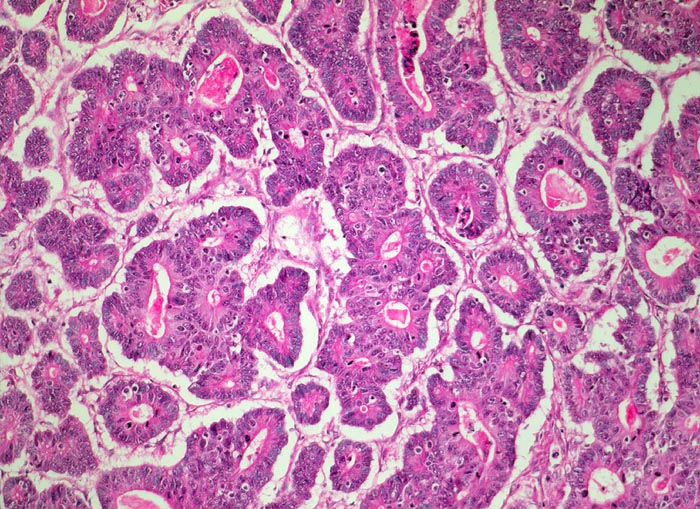

Weiter oben Invasion der Magenschleimhaut durch ein teils solides, teils drüsenbildendes Adenokarzinom mit stark atypischen Tumorzellen.

Der invasive Karzinomanteil zeigt teilweise muzinöse Differenzierung (teils siegelringzellige Tumorzellen schwimmen in extrazellulären Schleimseen).